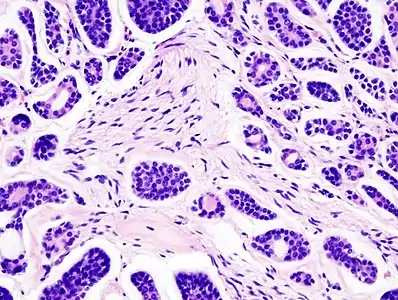

Histopathological image of adenoid cystic carcinoma of the salivary gland infiltrating a nerve (center), H&E stain